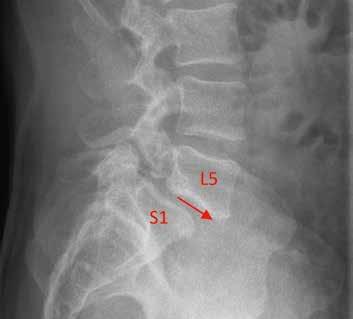

Een spondylodese is een operatie waarbij twee of meerdere wervels worden vastgezet. Zo’n fusie is een bewezen effectieve methode voor het verminderen van pijnklachten en het verbeteren van het functioneren bij een lumbale spondylolisthesis. Met behulp van observationeel onderzoek wordt in Nij Smellinghe sinds 2021 geprobeerd de patiëntreis rondom deze ingreep te verbeteren. Deze casus beschrijft het traject rondom de ingreep van een patiënt die een fusie kreeg op niveau L5-S1.

Wanneer een te grote beweeglijkheid van de wervels ontstaat, kan dit leiden tot instabiliteit van de wervelkolom. Deze instabiliteit kan veroorzaakt worden door een spondylolyse of een spondylolisthesis. Hierdoor raken zenuwen bekneld, wat kan leiden tot pijnklachten in de lage rug en sensorische en motorische stoornissen in één of beide benen. Door de betrok-

ken wervels te fixeren met behulp van osteosynthesemateriaal is de instabiliteit te verhelpen. Daarmee verbetert het lichamelijk functioneren en verminderen de pijnklachten.1 Deze ingreep wordt al vele jaren gedaan, maar wint de laatste tijd sterk aan populariteit. Er komen namelijk steeds meer moderne materialen beschikbaar die de ingreep veiliger en effectiever maken.2 In de Verenigde Staten is het aantal lumbale spondylodeses gestegen van 122.679 in 2004

Voorlichting en behandeldoelen De neurochirurg heeft Teun na het klinisch onderzoek en beeldvorming gediagnosticeerd met een anterieure afschuiving van L5 ten opzichte van S1 met indicatie voor een minimaal invasieve Transforaminal Lumbar Interbody Fusion (TLIF)-spondylodese ter hoogte van L5-S1. Als aanvulling wordt Teun verwezen naar de fysiotherapeut voor een preoperatieve screening. Bij de fysiotherapeut krijgt Teun uitleg over de gehele patiëntreis en hoe hij zelfregie kan nemen in het traject voor, tijdens en na de operatie. Veel aandacht gaat uit naar pijneducatie en grenshantering. Daarnaast krijgt Teun aan de hand van een patiëntfolder uitgebreide voorlichting over de opnameperiode. De hierin beschreven oefeningen voor na de operatie worden ook doorgenomen. Bovendien komen de leefregels voor na de operatie aan bod. De eerste zes weken mag Teun niet langer dan twintig minuten achter elkaar zitten. Ook mag hij niet fietsen, zwemmen, autorijden en werkzaamheden verrichten die de rug belasten, zoals